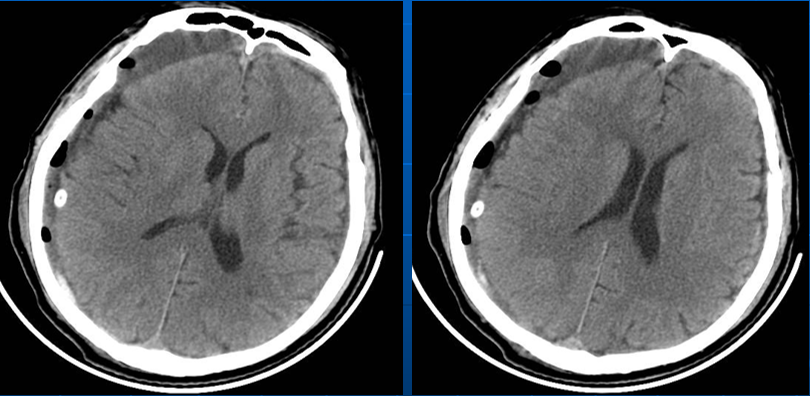

患者约2个月前无明显诱因(否认外伤史)间断出现头痛,头痛为胀痛,左侧较明显,恶心未吐,食欲、睡眠尚可,未予特殊诊治,1个月前患者头痛逐渐加重,思睡,反应略迟钝,行头部CT检查示“慢性硬膜下血肿(双侧)”,于2018年12月15日行颅骨钻孔引流术(左)。术后9天患者恢复良好出院。出院后2周于2019年1月9日患者头痛再次加重,伴有反应迟钝,走路困难,疲乏无力再次就诊,头部CT示“慢性硬膜下血肿(右侧)”,当日再次行颅骨钻孔引流术(右)。术后患者一般状态逐渐好转,无抽搐,无尿便失禁。

2018年12月16日术后第一日

自诉头痛明显缓解。查:神清语明,血压145/85mmHg,颈软,四肢肌力V级。